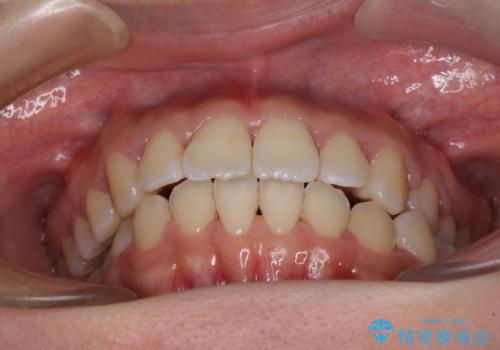

軽微な歯列不正をワイヤー矯正で整える

- 上顎歯列と下顎前歯の叢生を気にして来院された患者様です。

上顎からワイヤー矯正を開始し、終了間際から下顎前歯の叢生解消するよう計画しました。

部分矯正でしたが、咬み合わせに違和感が出ることなく気になる部分を改善させることができました。